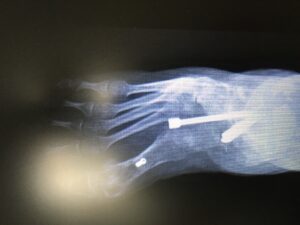

Skomplikowana operacja odtwórcza. Trzeba podczas operacji wyobrazić sobie nową konstrukcję stopy, żeby wytrzymała obciążenie, była bardziej funkcjonalna – no i piękniejsza.

Wykonałem potrójną artrodezę oraz usztywnienie stawu skokowego górnego w skorygowanym ustawieniu.